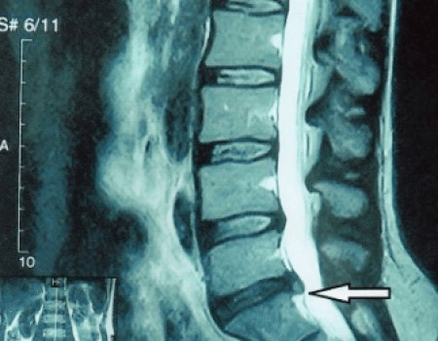

In typical cases, osteochondrosis of the cervical and cervical thoracic spine occurs, as described above.Therefore, the main phase of diagnosis was and remains to identify the patient's complaints and determine the presence of accompanying muscle spasms by simply palpating the muscles along the spine.Is it possible to confirm the diagnosis of osteochondrosis by X-ray examination?

An “X-ray” of the cervical spine and even functional tests for flexion and extension do not show cartilage because its tissue allows X-rays to pass through.Nevertheless, based on the location of the vertebrae, one can draw general conclusions about the height of the intervertebral discs, the general straightening of the physiological curvature of the neck - lordosis - as well as the presence of marginal growths on the vertebrae with prolonged irritation of their surfaces by brittle and dehydrated intervertebral discs.Functional tests can confirm the diagnosis of cervical spine instability.

Since the intervertebral discs themselves are only visible using CT or MRI, magnetic resonance imaging and X-ray computed tomography are indicated to clarify the internal structure of cartilage and formations such as bulges and hernias.Thus, with the help of these methods, an accurate diagnosis is made, and the tomography result is an indication and even an actual guide for the surgical treatment of an inguinal hernia in the neurosurgical department.

- You can regularly take at least one x-ray of the lumbar spine in two projections or an MRI to determine whether the hernia, if any, is progressing;